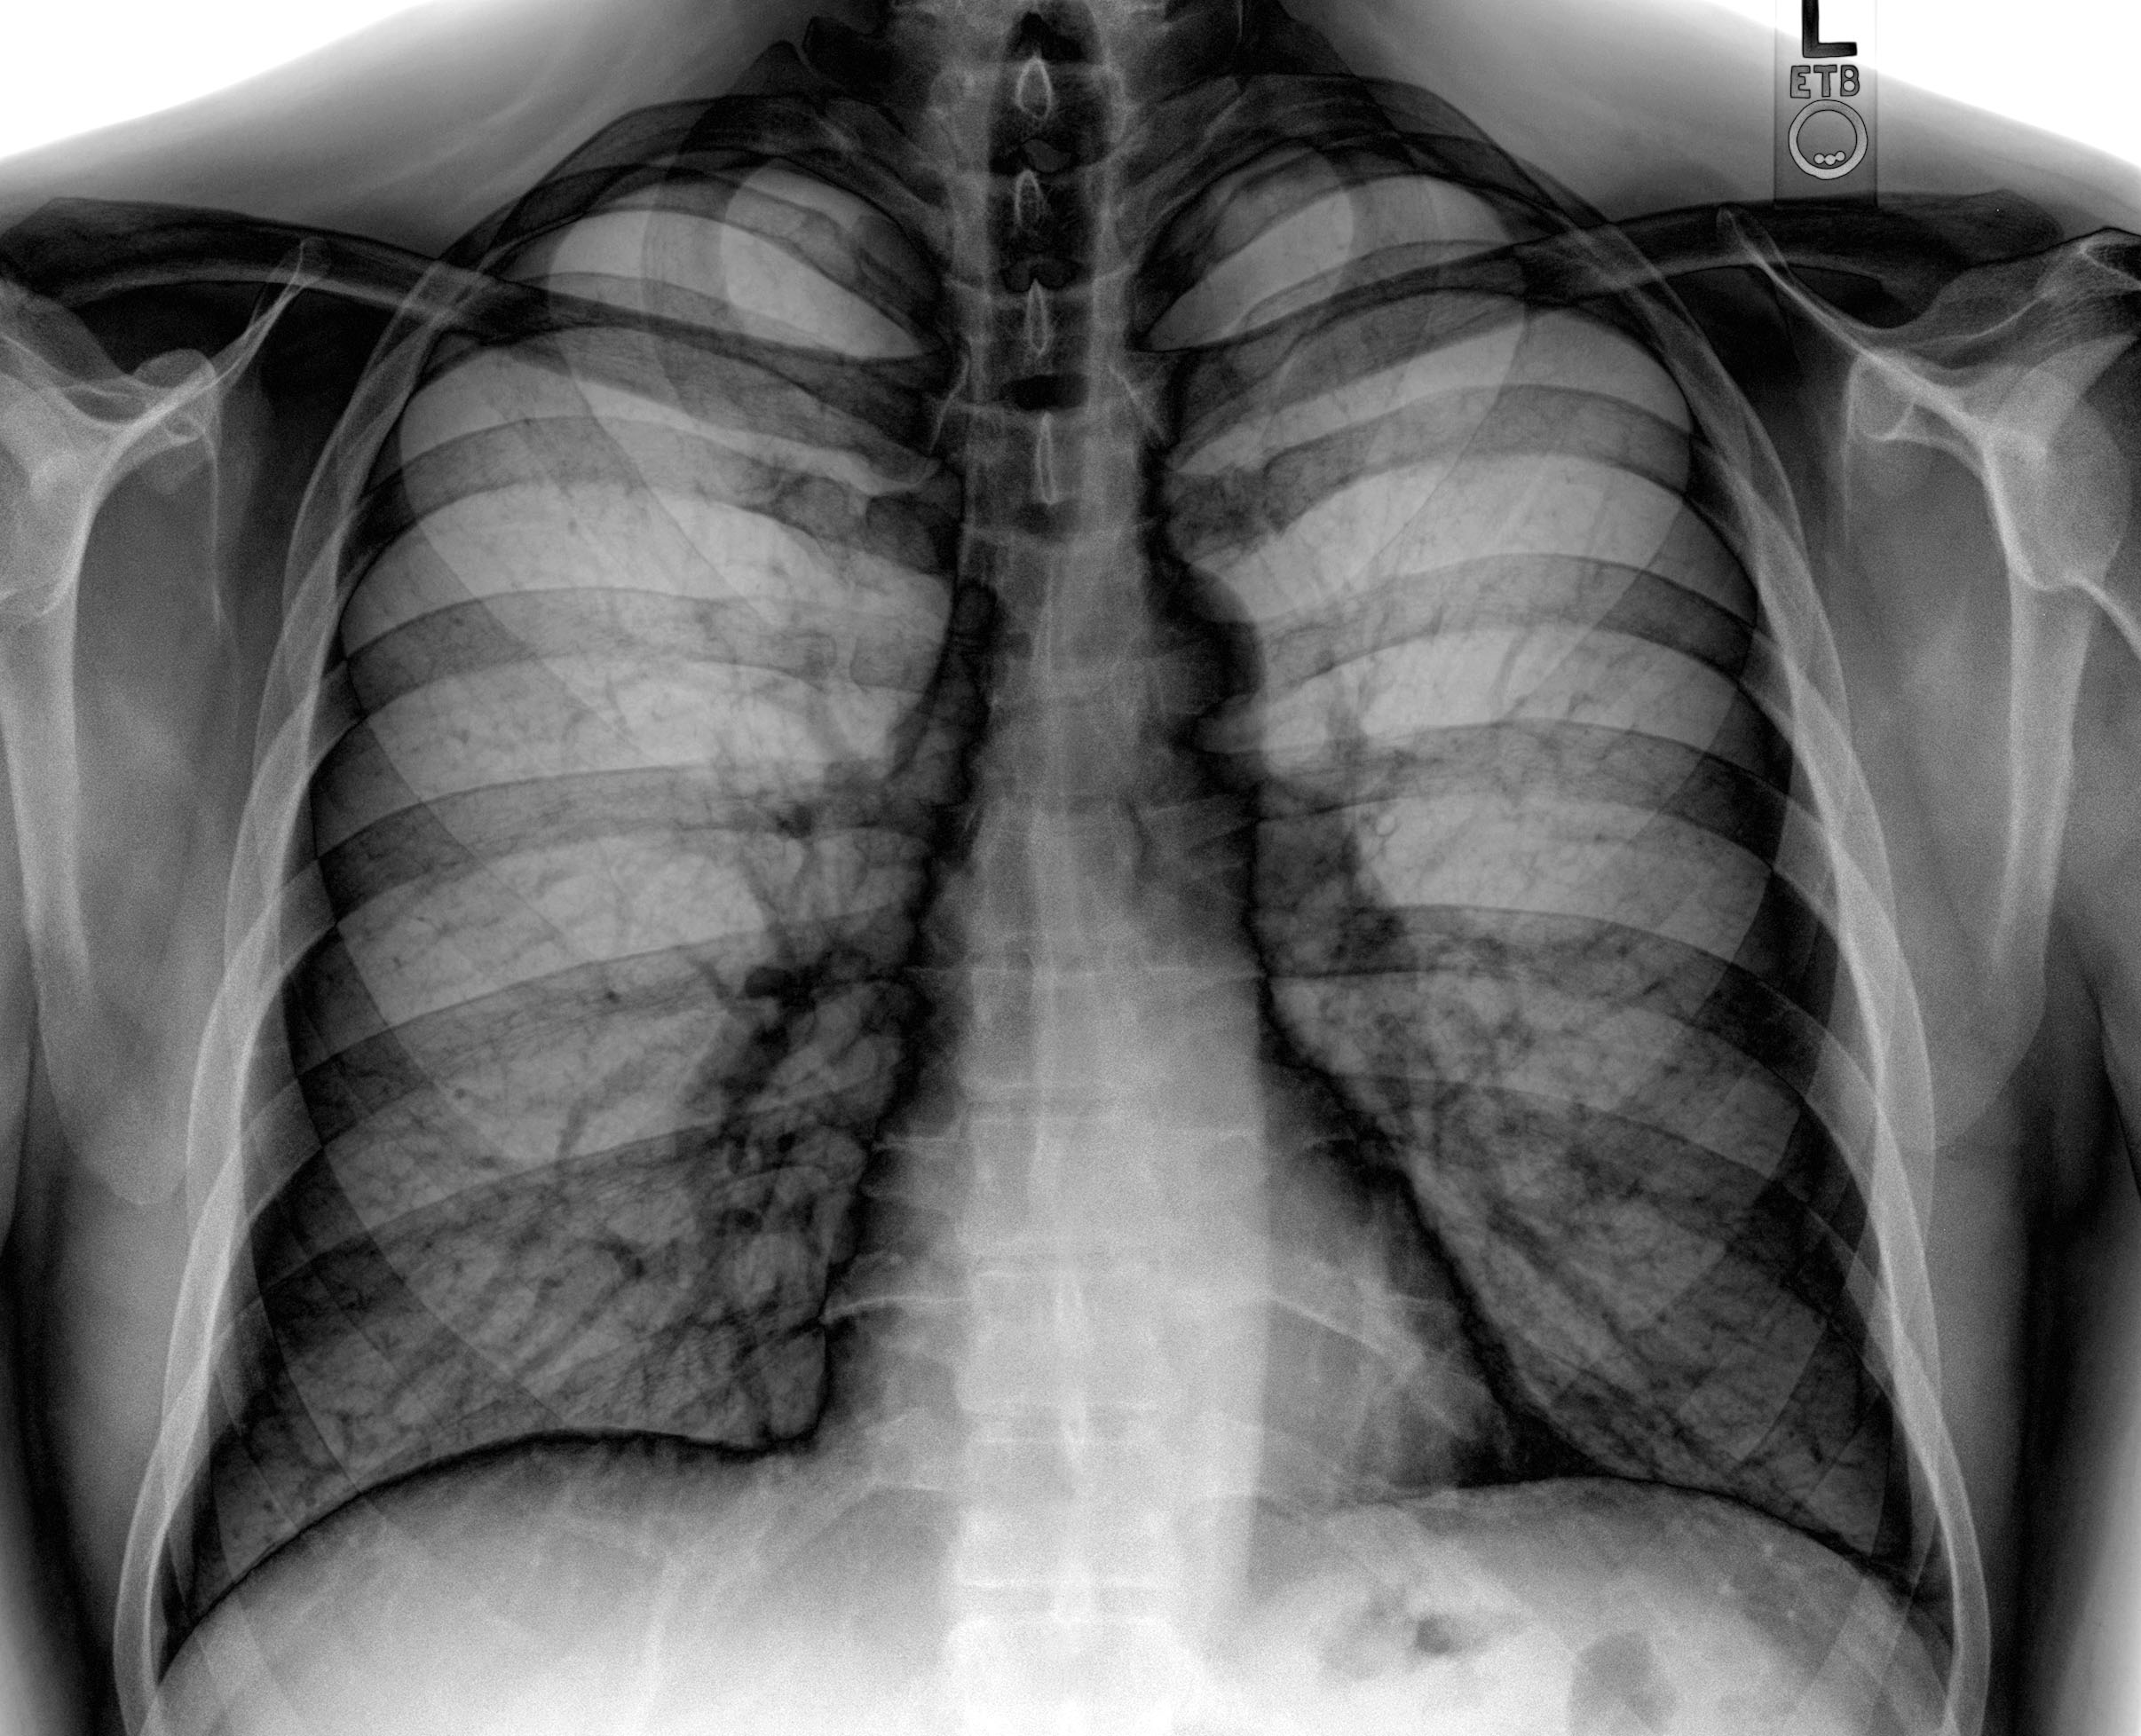

如当骨折发生时,X射线就像是一束神奇的光,穿透身体,将骨骼的影像清晰地呈现在胶片或数字探测器上,帮助医生迅速定位骨折位置,判断骨折类型,从而制定出科学的治疗方案。而CT扫描则更加精细,它从不同角度对身体进行X射线扫描,通过计算机处理,生成身体内部的横截面图像,让脑出血、脑肿瘤等微小病变无处遁形。

病变诊断影像